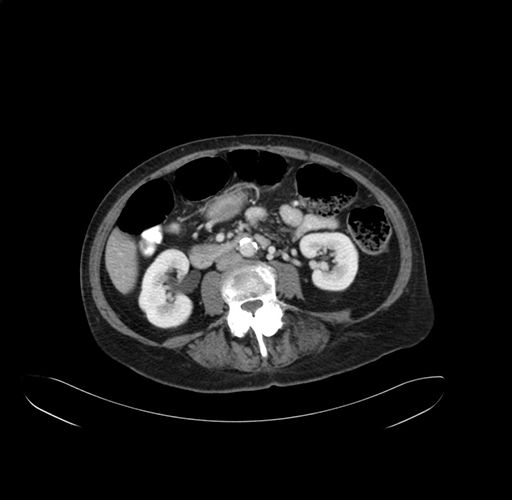

Pre-Chemo: Axial Venous

Axial Venous